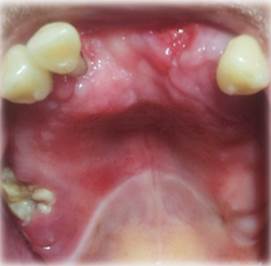

En el examen físico extraoral se observó frente prominente, tercio medio facial disminuido, hombros plegados con tórax excavado, dedos en forma de palillo de tambor, piel delgada y reseca, hiperfuncionalidad de la articulación del hombro. Mientras tanto, en la revisión estomatológica se observaron labios delgados, semi mucosas labiales con múltiples escamas y surcos labiales marcados, zona eritematosa intensa en mucosa palatina de paladar duro, con aspecto granular, halo blanquecino que delimita paladar duro del blando (Imagen 1); encía marginal y adherida con fuerte inflamación, eritematosa, engrosada, lisa y brillante de forma generalizada (Imagen 2); recesión gingival a nivel de encía marginal palatina y vestibular de órganos dentarios superiores. En la prueba de movilidad dental se evidencia movilidad horizontal y axial generalizada grado II y III para los órganos dentarios inferiores y II para los superiores.

A nivel de los rebordes alveolares superior e inferior se observó y palpó irregularidad acentuada en zona anterior, asociada a múltiples exodoncias realizadas en esta región de los maxilares.